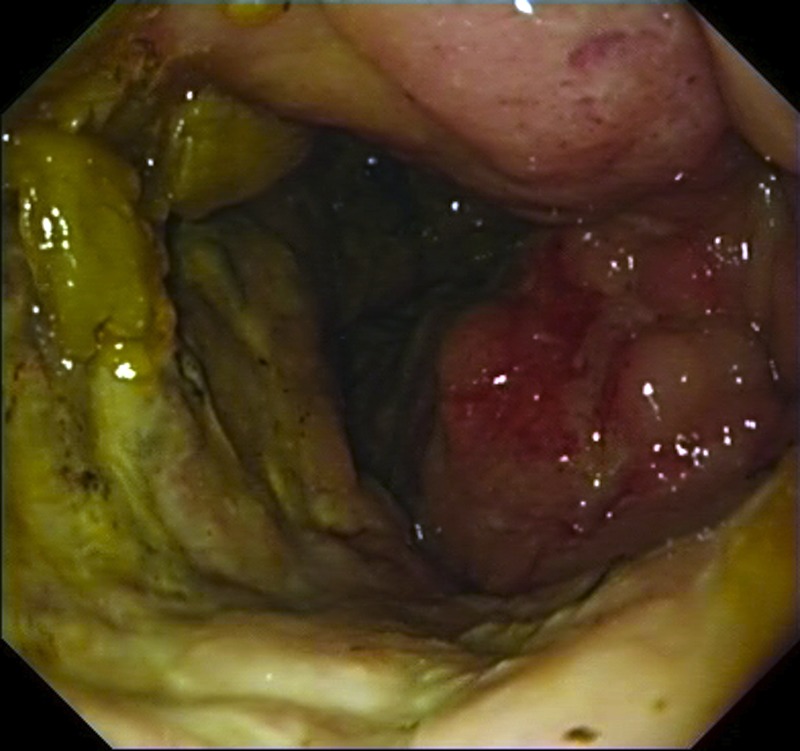

Κολονοσκόπηση. Ευδιάκριτα ευρήματα ισχαιμικής κολίτιδας (Ευγενική παραχώρηση Dr. V. Penopoulos)